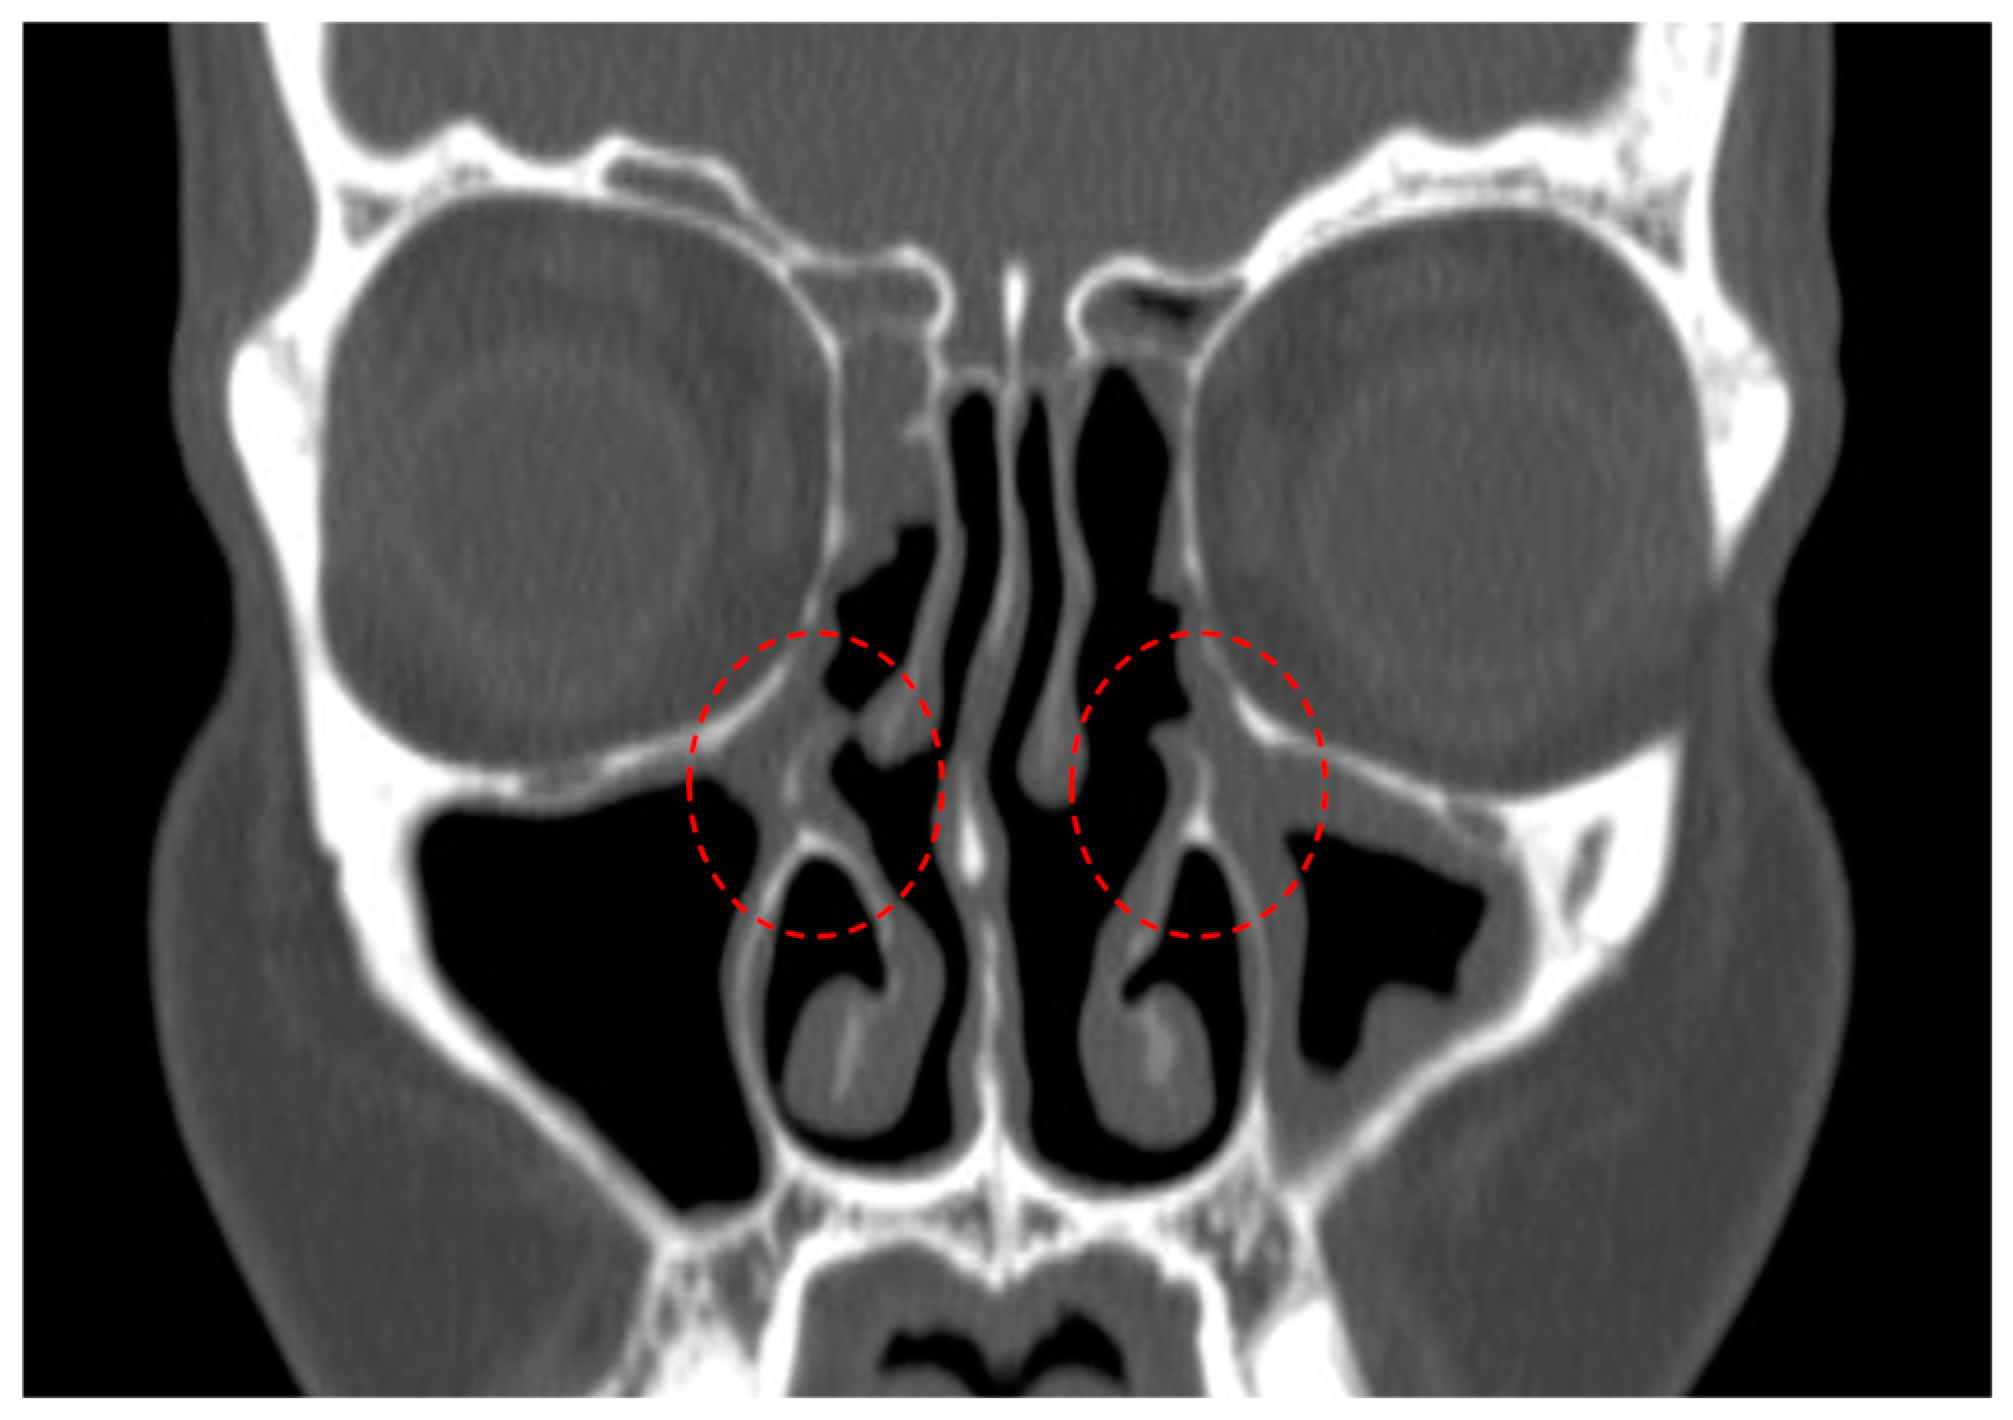

- Residual uncinate process (Figure 1);

| Residual uncinate tissue | 35 (50.7%) | 15 (42.8%) |